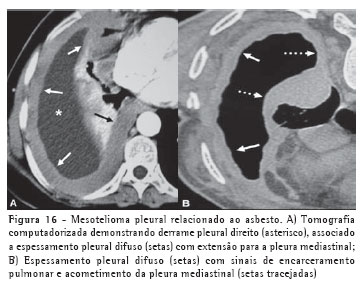

MesoteliomaApesar de haver descrições de mesotelioma em indivíduos com inflamação pleural crônica ou com história de exposição a carcinógenos químicos, a exposição ao asbesto está associada ao desenvolvimento do tumor em 50% a 80% dos casos. Dentre os achados radiológicos, o derrame pleural, geralmente unilateral, é o mais comum.

Podem também ser encontradas massas pleurais sólidas e espessamento pleural circunferencial com tendência a encarceramento pulmonar. A TC é o método de escolha na avaliação da presença e extensão do mesotelioma, apesar de os sinais não serem patognomônicos. Além destes achados descritos na radiografia, podemos encontrar espessamento irregular das fissuras, extensão para a pleura mediastinal, pericárdio e parede torácica e sinais de comprometimento à distância, como linfonodomegalias mediastinais, diafragmáticas e mamárias internas, e metástases linfáticas e hematogênicas (Figura 16).(21-22)